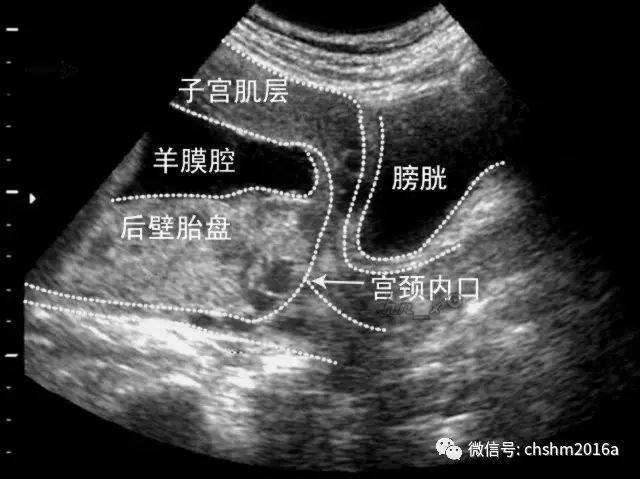

2.超声检查可以清楚显示子宫壁、胎先露、胎盘和子宫颈关系,以明确诊断。